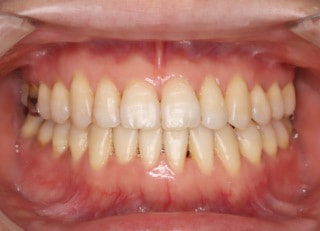

治療後(2年4ヶ月後)

治療後セファロ分析

ほぼ正常値に治り良好な状態です。

治療後セファロ分析正貌

下顎の偏位は改善されました。